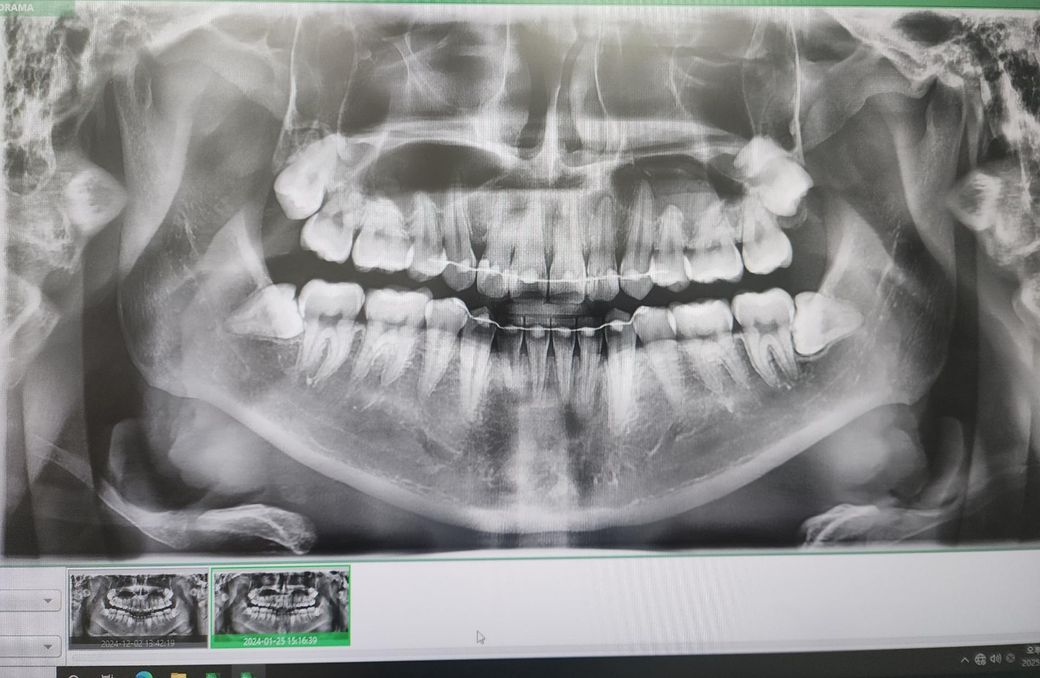

치과의사분들 파노라마 사진 해석부탁드립니다

사진상 앞니 오른쪽 뿌리끝에 작은 염증이 있다고 합니다

사진은 24년1월 24년 12월 25년 5월 순입니다

염증이 커지는 상황일까요?

아픈곳이나 시린곳은 없습니다 치료해야된다고 보시나요

엑스레이 상으로는 크게 염증이 커지거나 그렇진 않은거 같습니다. 증상이 없다면 정기적으로 치과를 다니시면서 관리를 받으시면될것같습니다.

사진상으로는 염증이 명백히 보이지만 증상이 없다면 일단 지켜보는 것도 괜찮을 것 같습니다.

파노라마 사진상으로 측은단 부위에 병소가 보이고 있습니다. 정확한 확인을 위해서는 CT 촬영을 해보는 것이 좋을 것으로 생각되며 치근단 질환이 생겼다는 것은 근관 내가 이미 감염이 되었다는 것이기 때문에 치근단 질환이 있다면 신경 치료를 해줘야 합니다. 그렇지 않다면 주변에 있는 치조골이 손상되어 나중에는 치아를 손실 할 수도 있습니다.